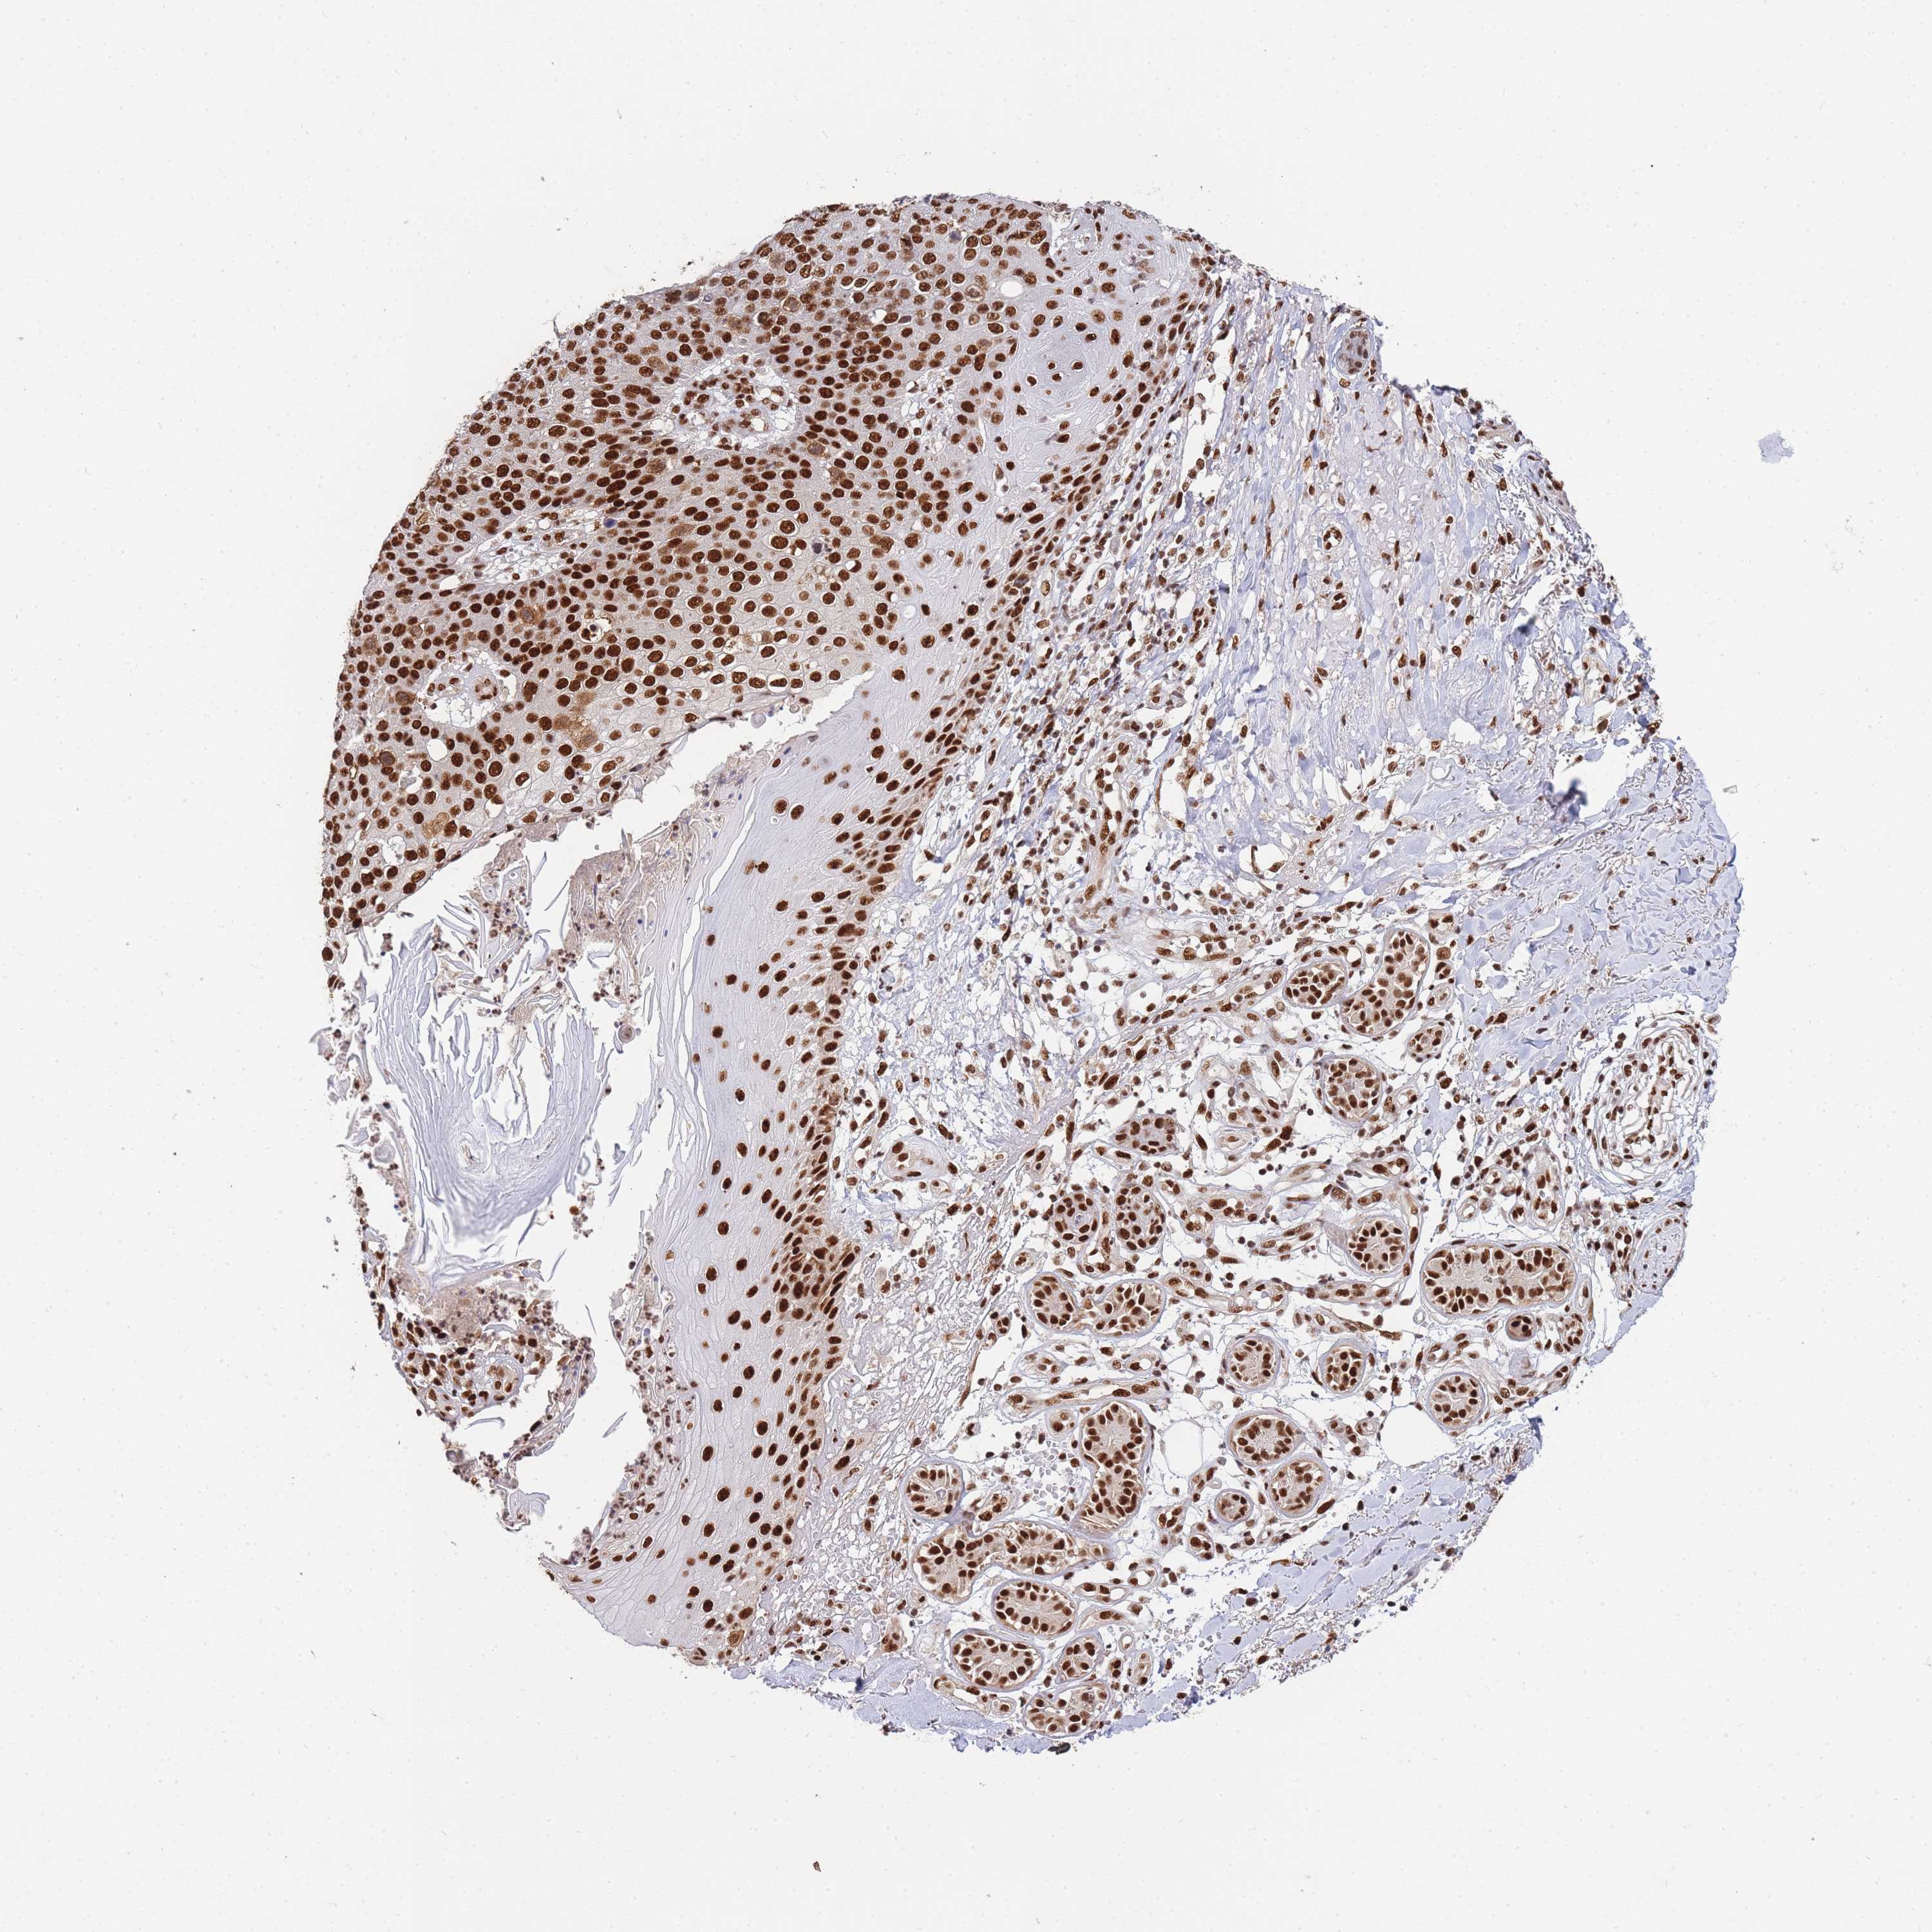

Basal cell and squamous cell cancer

SKIN CANCER - Protein expressioni

A mouse-over function shows sample information and annotation data. Click on an image to view it in a full screen mode. Samples can be filtered based on level of antibody staining by selecting one or several of the following categories: high, medium, low and not detected. The assay and annotation is described here.

Antibody stainingi

Antibody staining in the annotated cell types in the current human tissue is reported as not detected, low, medium, or high, based on conventional immunohistochemistry profiling in selected tissues. This score is based on the combination of the staining intensity and fraction of stained cells.

Each image is clickable and will lead to virtual microscopy that enables deeper exploration of all samples and also displays staining intensity scores, fraction scores and subcellular localization as well as patient and tissue information for each sample.

Antibody HPA035174

Antibody CAB005167

Staining

High

Medium

Low

Not detected

Intensity

Strong

Moderate

Weak

Negative

Quantity

>75%

75%-25%

<25%

None

Location

Nuclear

Cytoplasmic/membranous

Cytoplasmic/membranous,nuclear

Squamous cell carcinoma, metastatic, NOS